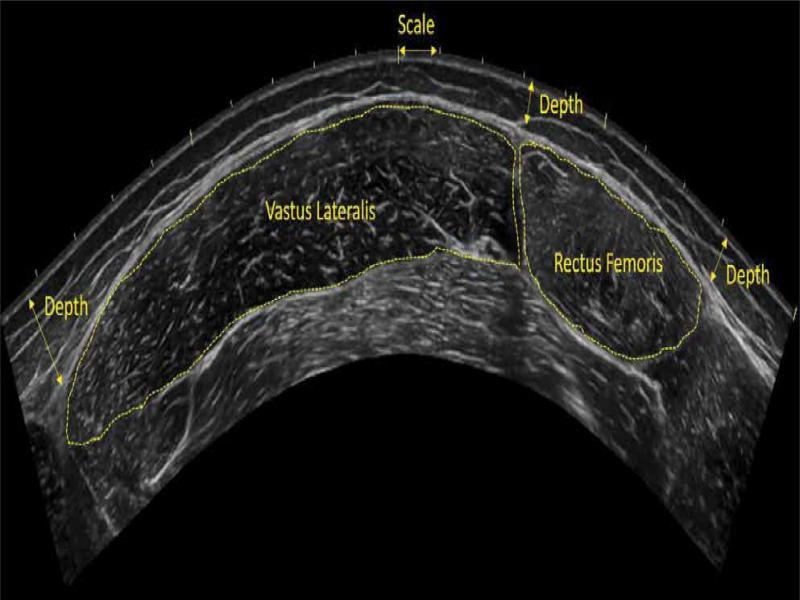

Fig. 1.